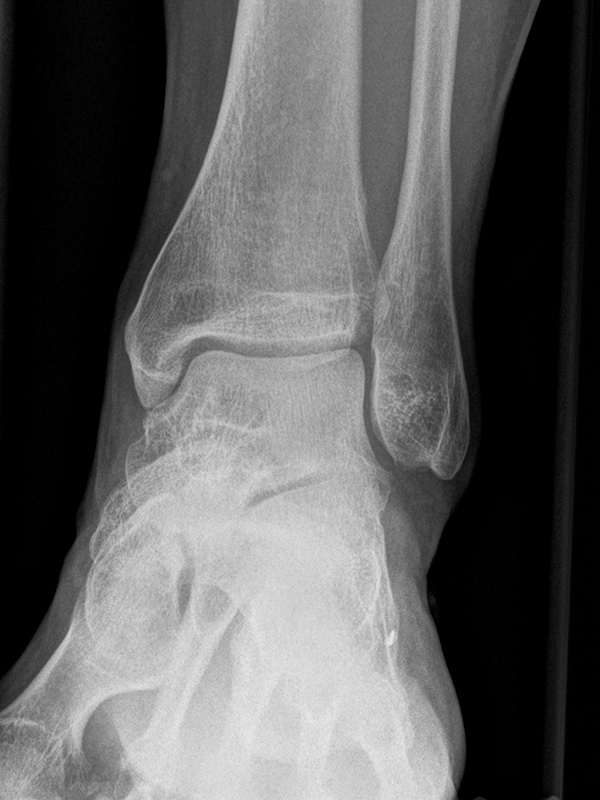

Sprunggelenk lateral mit Belastung

Positionierung:

• Der Patient steht, beide Beine sind geleichmäßig belastet.

• Der Zentralstrahl wird ist in Höhe des Gelenkspalts des OSG auf die dorsale Kante der Fibula zentriert.

• Die Kassette liegt medial dem Fuß an und ist parallel zur Fußachse ausgerichtet.

Kennzeichen des Röntgenbildes:

• Tibiagelenkfläche und Talusrolle werden exakt seitlich dargestellt, es kommt zu keinen Doppelkonturen.

• Die Fibula projiziert sich ins mittlere bis hintere Drittel der Tibiagelenkfläche.

• Die vordere und hintere Tibiakante, das Chopart-Gelenk und das Subtalargelenk kommen zur Darstellung. Das proximale Ende des Os metatarsale V ist mit abgebildet. Der Weichteilmantel (Achillessehne) ist erkennbar.

• In der belasteten Situation kommen insbesondere Verschiebungen von Talus gegenüber der Tibia zur Darstellung sowie eine Verschmälerung des Gelenkspalts.

Besondere Bemerkungen zum Beispielbild:

• Zustand nach Fremdkörperverletzung (2. Ebene zur Mortise-Aufnahme unter Belastung).

• Die röntgendichte Struktur (Metall) befindet sich plantar im Bereich des Kalkaneus.